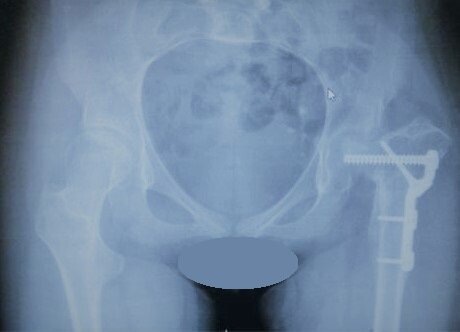

Рентгенография и КТ до операции (вывих левого бедра, разрушение головки бедра с полной потерей сферичности)